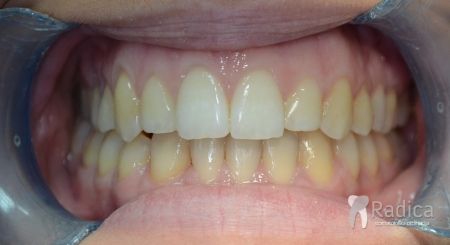

U sljedećem primjeru su se na mjesto donjih ekstrahiranih prvih molara stavili dentalni implantati prije ortodontske terapije (rad dr. Gorana Radice) i ujedino su služili za pojačenje sidrišta tijekom ortodontske terapije. Nakon ortodontske terapije estetski su se preoblikovali sjekutići i napravile nove krunice (također rad dr. Gorana Radice).